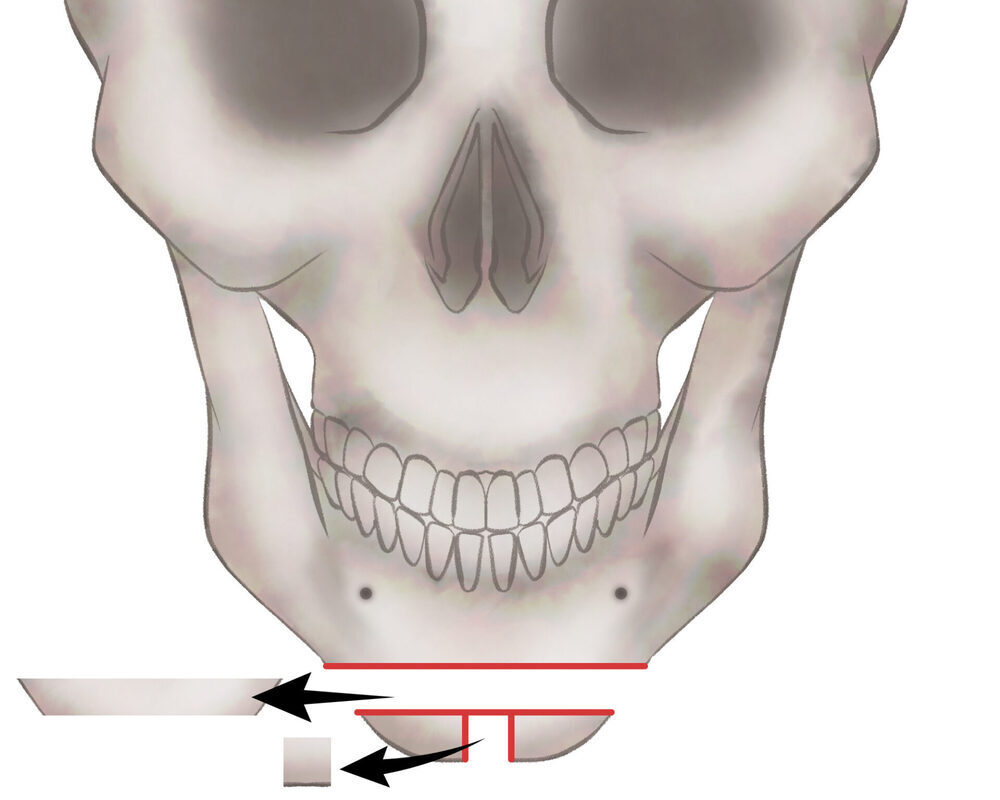

オトガイ骨切り(中抜き)

2.骨を切除します

3.骨を移動させ段差を削ります

4.プレートで固定します